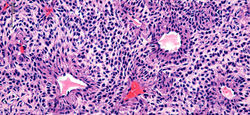

Histológicamente corresponde a una neoplasia mesenquimal compuesta por tres elementos: células glómicas, vasos sanguíneos y células musculares lisas convencionales(1,5). La proporción de estos componentes ha dado origen a la clasificación morfológica de tumor glómico sólido (con escasa vasculatura y músculo liso), glomangioma (con prominente componente vascular) como en este caso y glomangiomioma (con predominio tanto de componente vascular como muscular liso)(1). La forma de tumor glómico sólido es la más frecuente encontrada, seguido por los glomangiomas y los raros glomangiomiomas.

Generalmente se describen como una lesión compuesta por vasos ramificados tapizados por células endoteliales sin atipias, separados por una población de células redondas de núcleo central (generalmente con pseudoinclusión) y citoplasma eosinófilo, dispuestas formando nidos, sábanas o trabéculas, presentando una distribución perivascular muy característica(F5). Estas células presentan bordes nítidos, descansando sobre una matriz hialina(F4), no siendo raro encontrar incluso depósitos de mucina(1,5). La lesión se localiza a nivel dérmico(F1), con bordes definidos, no encapsulada, generalmente relacionada con un vaso sanguíneo o una red vascular fácilmente identificable(F2-3)(1). Pese a su aspecto epitelioide y su íntima relación con la vasculatura, estas células son positivas para marcadores musculares como AML(F6), H-caldesmon o calponina, sin expresión de marcadores epiteliales. Los marcadores endoteliales como CD34(F7), CD31, ERG, resaltan el componente endotelial que coexiste con la lesión(1,4,5).